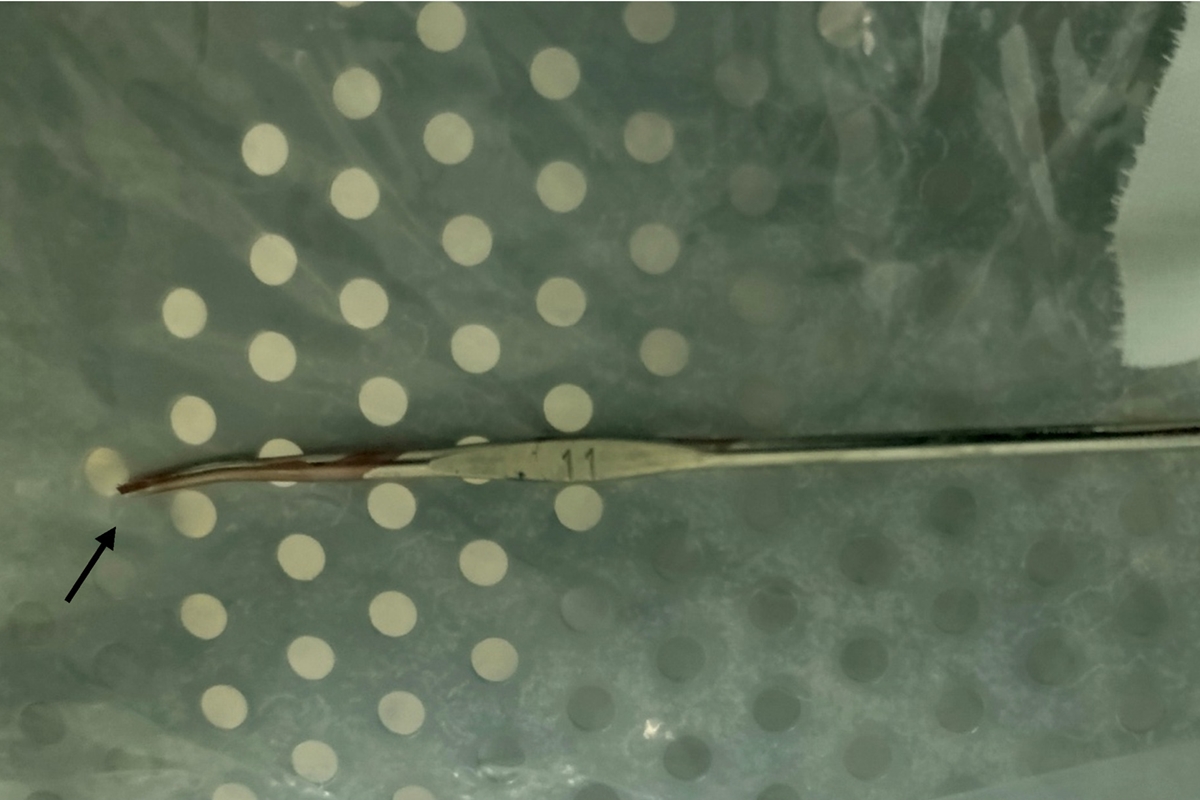

Curiosamente, apesar da profundidade de entrada do objeto nº11, quando o menino chegou ao hospital após o acidente, não escorria sangue da ferida e nem tinha alteração urinária. Um raio X foi feito indicando a profundidade do objeto e os melhores meios de retirada durante a cirurgia.

Após uma anestesia local, a equipe retirou a agulha com uma incisão que permitiu cortar o metal do objeto para movimentá-lo levemente. O método possibilitou a retirada do objeto com pinças evitando danos maiores aos tecidos do menino.